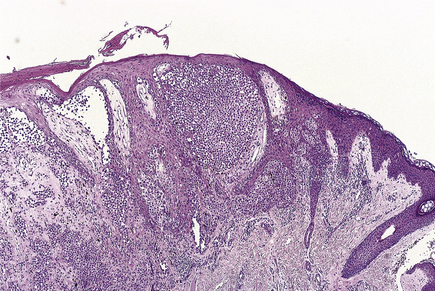

The lesions are commonest on the extensor surfaces (Fig. 24.6), such as the knees and elbows, and the first appearance may be in a site of trauma such as a surgical wound—a phenomenon known as the Koebner effect. The clinical lesions are termed plaques, meaning slightly palpable and elevated areas, often measuring over 50mm. The individual lesions are covered with a silvery scale and scraping the scale off reveals a series of small bleeding points (Auspitz’s sign).

image

Fig. 24.6 Psoriasis. This inflammatory condition has a strong genetic tendency. It is characterised by silvery scales of parakeratosis and bleeding when scratched superficially. The lesions show a predilection for extensor surfaces and are uncommon on the face.

Histologically (Fig. 24.7), the normal pattern of rete ridges becomes thickened (acanthotic) and the dermal papillae are covered only by a thin layer of epidermis two or three cells thick. This accounts for the bleeding points seen when the scale is scratched off. The progress of the epidermal cells through the epidermis is speeded up and maturation is incomplete. This is reflected in the accumulation of abnormal keratin with nuclear fragments (parakeratosis) in the form of the silvery scales. The maturation of the keratin is so disturbed that the normal granular layer of the epidermis is lost (Fig. 24.7). The erythema is caused by dilated vessels in the upper dermis and these can be seen to contain numerous polymorphs which migrate from the vessels into the epidermis, sometimes in sufficient numbers to form actual pustules. These sterile pustules may dominate the clinical picture in one variant of the disease (pustular psoriasis) and this presentation is often marked when the disease appears on the palms of the hands or soles of the feet.

Fig. 24.7 Psoriasis. A common, inherited inflammatory condition of the skin, of unknown aetiology. The progression of the lesion from normal skin to the healed lesion is shown from left to right.